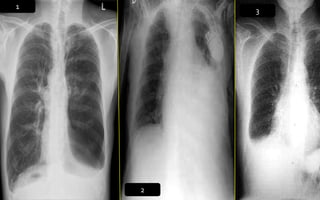

CASOS PATOLOGICOS

1. Marcado aumento del

índice cardiotorácico.

2. La punta del corazón

se dirige al diafragma

por dilatación

biventricular.

3. Aumento del tamaño

de la aurícula derecha.

1. Aumento del índice

cardiotorácico.

2. APEX se dirige hacia abajo del

diafragma por dilatación delVI.

3. Aumento de la densidad

pulmonar bilateral con

distribución perihiliar y basal,

aspecto algodonoso,

confluente, límites mal

definidos borrosidad vascular

(InfiltradoAlveolar).

Radiografía de tórax

Patrón lobarBronconeumoníaNeumonía intersticialAbsceso pulmonarPatrón nodular

Southwick F. Pulmonary infections. In: Infectious diseases a clinical short course. LANGE. 2014